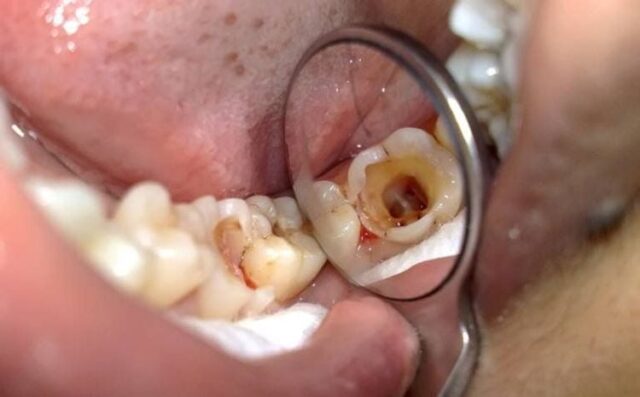

Tủy răng chết hay tủy răng hoại tử là tình trạng tủy răng bị tổn thương không hồi phục, dẫn đến sự ngừng hoạt động của các dây thần kinh và mạch máu bên trong. Khi tủy răng chết, răng sẽ không còn khả năng cảm nhận nhiệt độ, áp lực và đau đớn nữa. Tủy răng chết có thể xảy ra ở cả răng cửa, răng hàm và răng nanh.

Nguyên nhân dẫn đến tình trạng tủy răng chết rất đa dạng, nhưng phổ biến nhất vẫn là sâu răng không được điều trị kịp thời. Sâu răng ăn sâu vào ngà răng, xâm nhập vào buồng tủy và gây nhiễm trùng, dẫn đến viêm tủy răng và cuối cùng là tủy răng chết. Chấn thương răng cũng là một nguyên nhân quan trọng, đặc biệt là khi chấn thương gây ra gãy răng hoặc tổn thương nghiêm trọng đến tủy răng.

• Sâu răng nặng: Đây là nguyên nhân hàng đầu dẫn đến tủy răng chết. Sâu răng không được điều trị sớm sẽ ăn sâu vào ngà răng và xâm nhập vào buồng tủy, gây nhiễm trùng và viêm tủy răng.

• Điều trị tủy (root canal): Đây là phương pháp điều trị phổ biến nhất. Nha sĩ sẽ loại bỏ phần tủy răng bị nhiễm trùng, làm sạch và khử trùng buồng tủy, sau đó trám lại buồng tủy bằng vật liệu chuyên dụng. Điều trị tủy răng chết giúp bảo tồn răng và ngăn ngừa biến chứng.